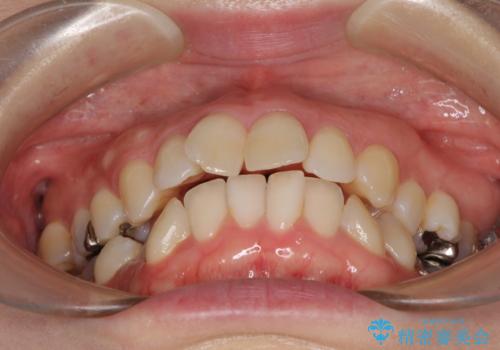

- 奥歯のむし歯を気にして来院された患者様です。

当初は右下の虫歯治療のみを希望されていましたが、虫歯治療に際して部分矯正が必要であったため、治療方法について説明をすると、全体的に歯列不正が気になっているとのことで、全顎矯正を検討することとなりました。

口元の突出感とデコボコがあり、上下左右の小臼歯4本を抜歯して矯正治療を行う方針としました。(右上は欠損のため計3本抜歯)

むし歯となっている歯は状態が悪く、将来的に抜歯となる可能性が高かったため、定石で抜歯させる小臼歯の代わりにむし歯となっている大臼歯を抜歯し、ワイヤー装置にて矯正治療を行うこととしました。